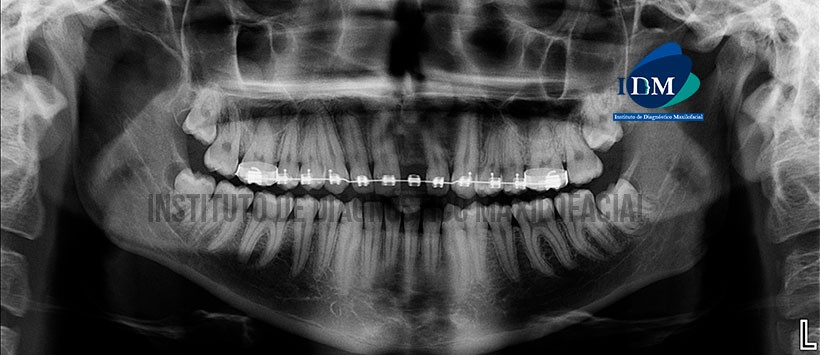

Paciente de sexo masculino de 18 años de edad acude al Instituto de Diagnóstico Maxilofacial para evaluación de terceras molares por motivo de exodoncia.

A la evaluación de la radiografía panorámica se evidencia aparatología fija para ortodoncia en el maxilar superior, leve apiñamiento dentario del sector anteroinferior, ausencia de la pieza 21 y terceras molares retenidas e impactadas. Siendo lo mas resaltante la imagen radiolúcida pericoronaria asociada a la cara distal de la pieza 48, la cual es de forma redondeada, con limites definidos y bordes corticalizados. (Figura 1)